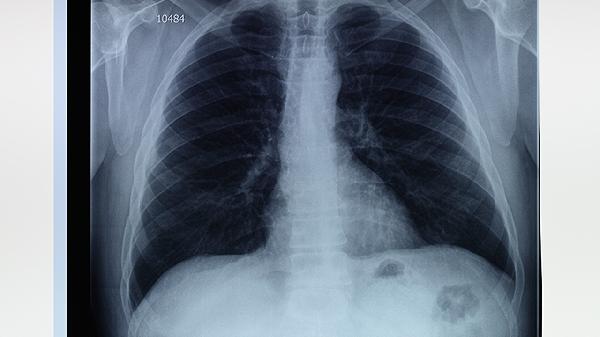

肺脓肿在我们日常生活中属于比较常见的一种疾病,中医称肺脓肿为“肺痈“,肺脓肿是由于多种病因所引起的肺组织化脓性病变。这个病给很多患者朋友非常大的烦恼,所以各位朋友一定要做好预防肺囊肿的措施。

肺对于人体来说非常关键,但如今的肺部疾病经常出现在我们的生活当中,很多肺脓肿患者都是急性发作,那么,患上肺囊肿应该怎样护理呢?以下小编给各位朋友介绍“肺脓肿的护理诊断肺脓肿应该怎样护理“。